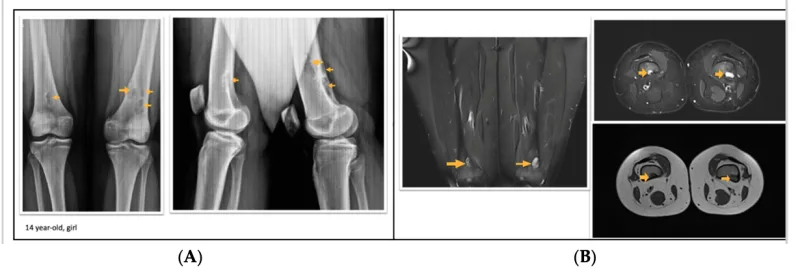

X線写真では, 大腿骨に孔が開いたように丸く透けて見える病変が認められます.

大腿骨の骨腫瘍が疑われる小学生が, 紹介で受診されました.

X線写真では, 大腿骨遠位部に孔が開いたような円形の透亮像を認め, MRIでも同部位に一致した信号変化を確認.

画像所見から, 『骨幹端線維性欠損(非骨化性線維腫)』と診断しました.

症状はなく. 成長とともに自然消失する良性の腫瘍類似疾患であることを説明し, 治療は不要としました.